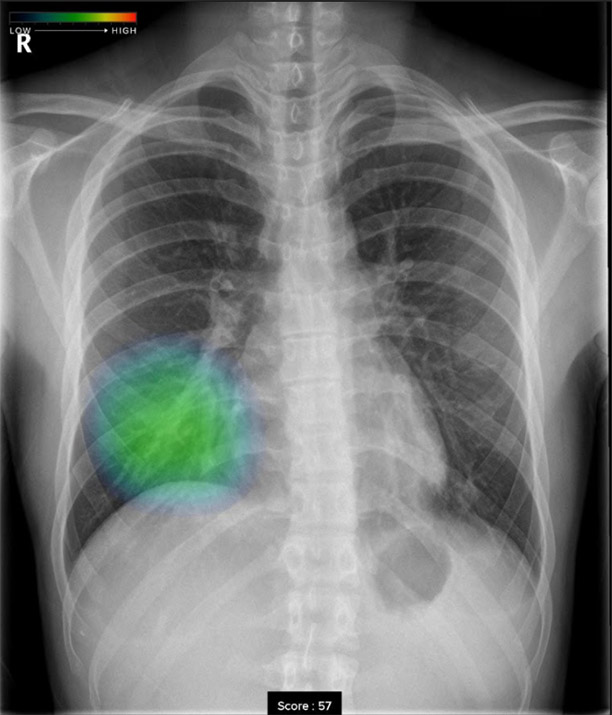

胸部レントゲン検査の場合、見る医師が少しでも異常がありそうと判断をしたら「要精査」とコメントし精密検査を行う流れになります。見落としがないように少しでも異常が疑われればやや過剰にでも異常と判断をいたします。そこでエルフ内科クリニックでは最新のAI技術を活用し、病変検出能が明らかに向上する「胸部X線画像病変検出ソフトウエアCXR-AID」を導入いたしました。

撮影画像を自動解析して、結節、腫瘤影、浸潤影、気胸が疑われる領域を検出しマーキングいたしますので、医師とAIがダブルチェックを行ない、診断精度を高めております。

• 浸潤影浸潤影